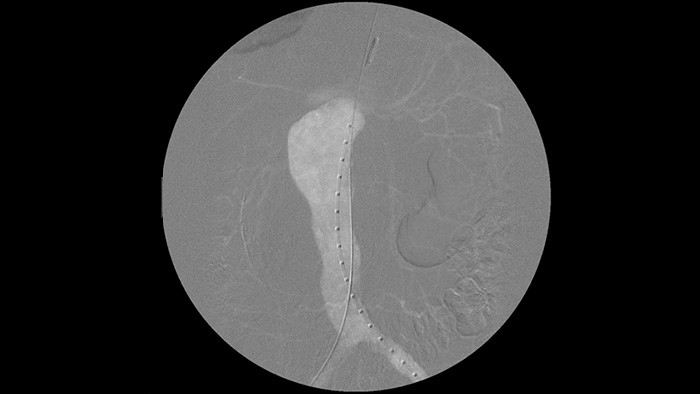

Цифровая субтракционная ангиография (DSA) используется в интервенционных сосудистых процедурах для четкой визуализации кровеносных сосудов путем удаления структур, которые могут снижать видимость сосудов. В рамках рентгеноскопии с картой сосудов ранее полученное субтракционное изображение с контрастированием накладывается на полученное рентгеноскопическое изображение в режиме реального времени, что позволяет отслеживать устройство без повторного введения контраста.

Благодаря Zenition качество изображения DSA значительно улучшилось. Изображение больше не зернистое, а четкое.